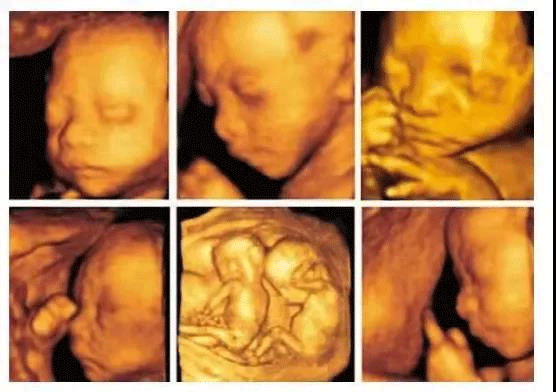

回答:孕期四维彩超是超声检查的一种,其成像技术能够让孕妇更加清晰的观察宝宝的生长发育情况。

除了对胎儿进行常规检查外,四维彩超和B超的区别在于其图像更加立体,能够对胎儿头面部立体成像,帮助医生动态观察宝宝神经系统情况,是孕早期胎儿排畸的重要检查手段,高档次的四维检查,还添加了时间维度参数,可以实时掌握胎儿活动图像。

在临床上,四维彩超的全称为四维彩色超声诊断仪,是目前世界上先进的超声检查设备,为胎儿是否有先天性心脏病、脊柱裂畸形等提供准确的科学依据,孕妇可以及早发现及时做处理,达到优生优育的目的。

3、面部是否存在畸形,我们都知道四维彩超的作用就是能够将胎儿的全身情况以非常清晰的形式展现出来,所以医生通过观察胎儿面部,测量双眼与眼眶是否等大、眼距信息、硬腭、软腭等,诊断脸部发育是否畸形;